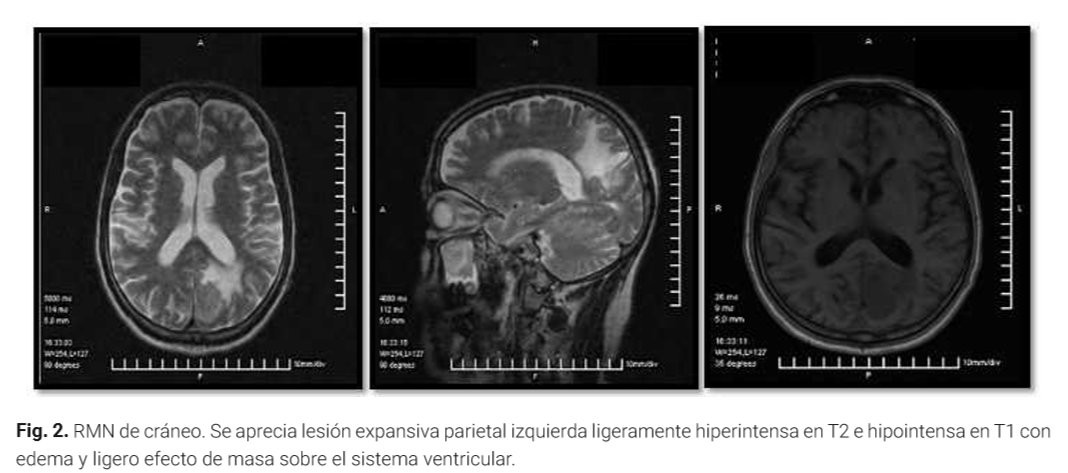

"Linfoma no Hodgkin células B primario del sistema nervioso central en paciente inmunocompetente" Presentación de caso clínico publicada recientemente y que pueden acceder al texto completo en: revistaccuba.sld.cu/index.php/reva… Hospital_Hermanos_Ameijeiras Ministerio de Salud Pública de Cuba Anales de la Academia de Ciencias de Cuba Dr.Cs. Luis C. Velázquez Pérez